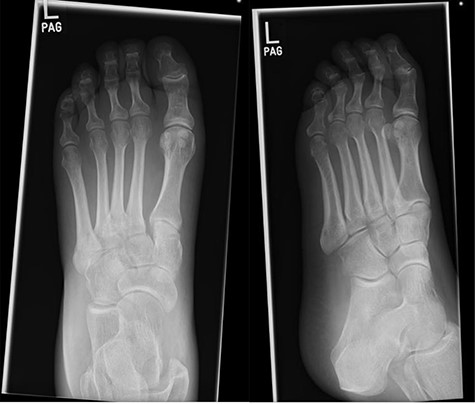

Post-operative X-rays (AP and lateral), demonstrating good reduction and fixation of fracture dislocations.

The patient was initially managed with a total contact leg cast, followed by open reduction and internal fixation (ORIF) with locking plates, combined with lengthening of the tendo-Achilles to permit full dorsiflexion and subsequent re-casting (Fig. 5). Her post-operative progress was satisfactory, and she is currently non-weight bearing for 6 months post-ORIF.